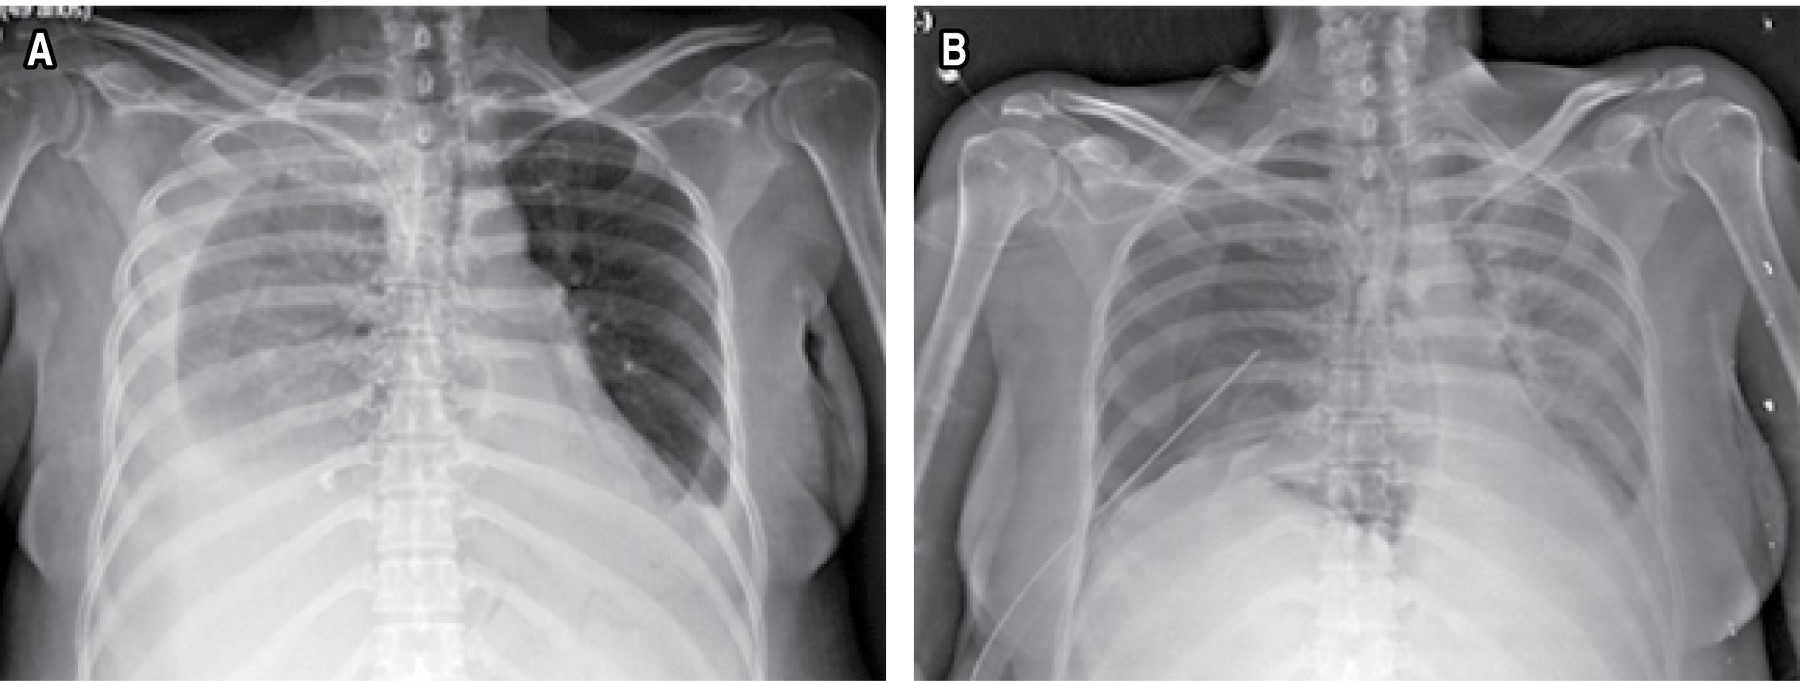

She was sent to our service on 10-27-19, receiving 85% oximetry and anasarca; a chest teleradiography was performed on admission, showing evidence of right pleural effusion of approximately 40%, placing a water seal in the sixth intercostal space with right axillary midline and verifying its placement with a control chest X-ray that ensures the placement of the probe, proposing an exploratory laparotomy on 10-29-19 (Figure 3).